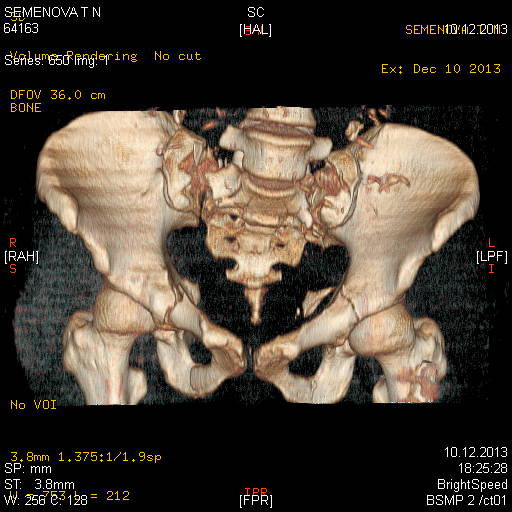

Доброго времени суток коллеги! Прошу вас, подсказать тактику в решении

оперативного лечения следующего сложного повреждения таза. Был ли опыт в

фиксации подобных повреждений?

Травма 03.12.2013,больная переведена из лечебного учреждения соседней

области. На данный момент у больной следующий диагноз: ЗЧМТ,сотрясение

головного мозга;Закр. травма грудной клетки,множественные переломы ребер

справа с повреждением ткани легкого, правосторонний гемопневмоторакс,

состояние после торакоцентеза; Закр.травма живота,разрыв

селезенки,гемоперионеум, состояние после лапаротомиии спленэктомии;

Закр. оскольчатый перелом сред-верх\3 левой бедренной кости, состояние

после накостного металлостеосинтеза; Закр.поперечный переломовывих на

уровне S1S2, многооскольчатый перелом латеральных масс крестца с обеих

сторон,перелом обеих лонных и седалищных костей.

Перелом поперечных отростков L1,L2,L3,L4, L5 позвонка справа. ШОК 3ст.

Вкратце изложил диагноз.

В настоящее время состояние больной тяжелое. Первым этапом планируем

наложить АНФ (переднюю раму) После стабилизации состояния необходимо

будет выполнить фиксацию.

Имеется один вопрос - какие импланты необходимы т.е. в какой комбинации

и какая последовательность фиксации?